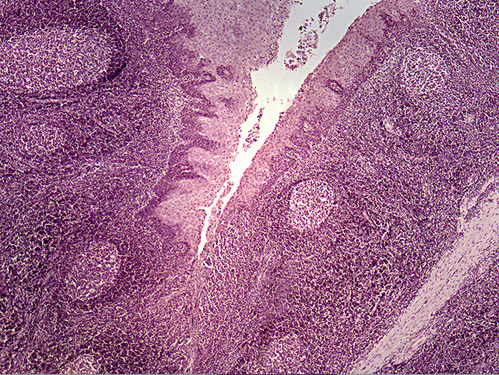

Areas of diffuse lymphatic tissue are found in the walls of the structures marked by the green arrows. They are called the///small intestine

The diffuse lymphatic tissue found in the structure marked by the green arrow is called peyer's PATCH

The green arrow is indicating the peyer's patch in this area of the small intestine. It is made up of a dense accumulation of what kind of cells?//lymphocytes

diffuse lymphatic tissue called peyer's patches in the wall of the intestinal tract.